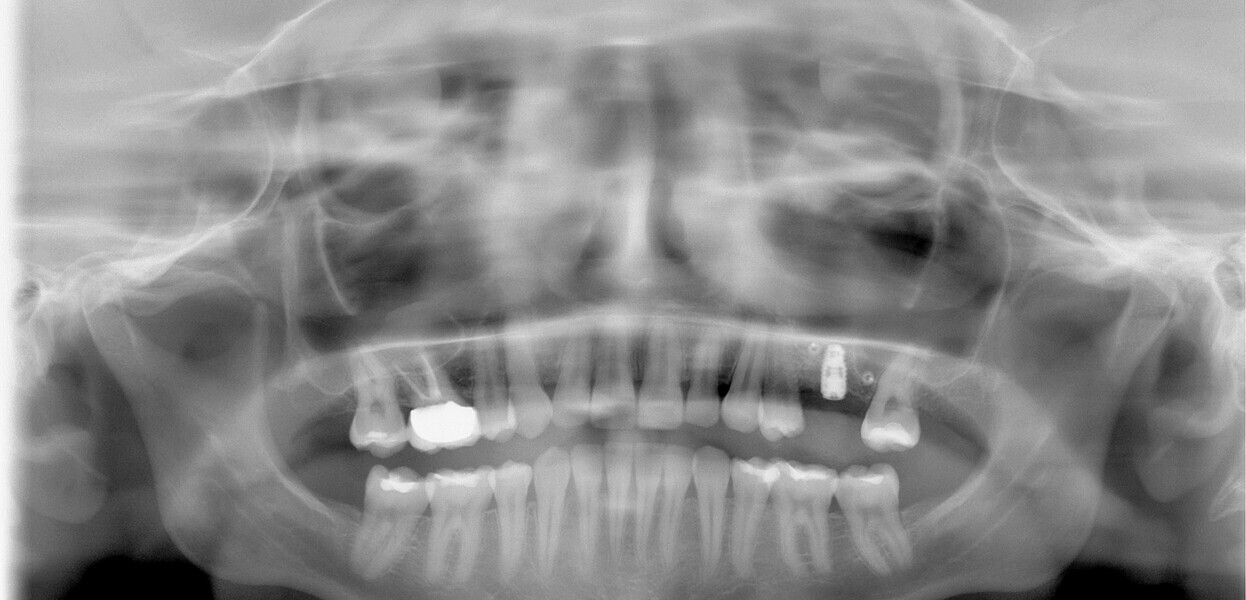

Fig. 13: Dental panoramic tomogram showing superstructure.